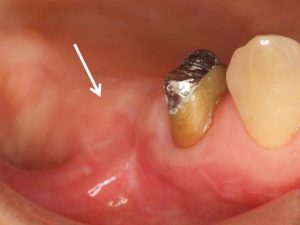

右側下顎小臼歯部の歯茎の腫れ。根管治療を数回行うも、頬側の歯茎の腫れが改善しない。難治性と判断し外科的に病巣を切除することにした。

根管治療をしっかりと行った後、歯茎を切開・剥離して病巣を取り除いた。